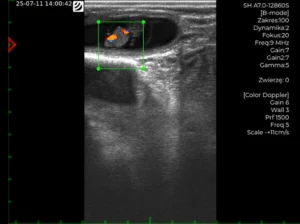

4. Capacidades Doppler ampliadas

• Doppler Color (CD) y Doppler de Potencia (PD) ya disponibles.

• Una vez activado el modo Doppler, aparece un cuadro Doppler en la pantalla.

• El cuadro puede moverse mediante las teclas de flecha.

• Pulse ESC para cambiar al modo de cambio de tamaño y, a continuación, ajuste el tamaño del cuadro con las teclas de flecha.